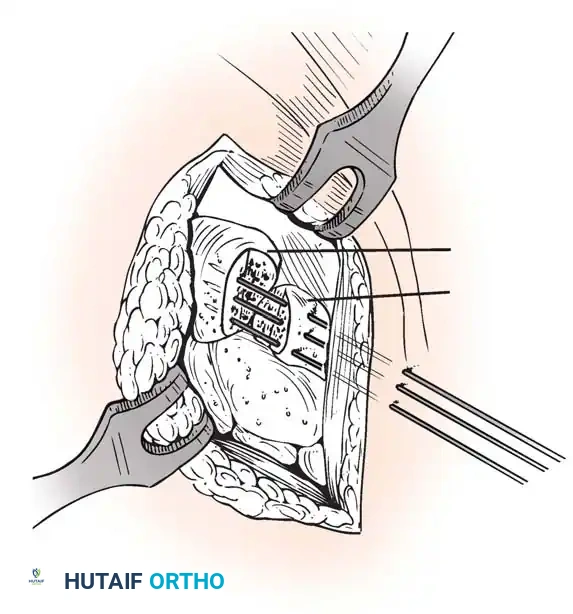

- Joint Preparation: The dorsal cartilage of the radiocarpal, intercarpal, and third carpometacarpal joints is meticulously denuded down to bleeding subchondral bone.

- Bone Grafting: A local distal radial bone graft portal is utilized. Cancellous bone is harvested from the distal radius metaphysis to augment the fusion sites.

- Plate Application: A 3.5-mm dynamic compression plate (DCP) is applied from distal to proximal. The plate is specifically contoured to provide 10 to 15 degrees of wrist extension. The plate spans the local radial bone graft augmentation, ensuring rigid compression across the fusion mass.